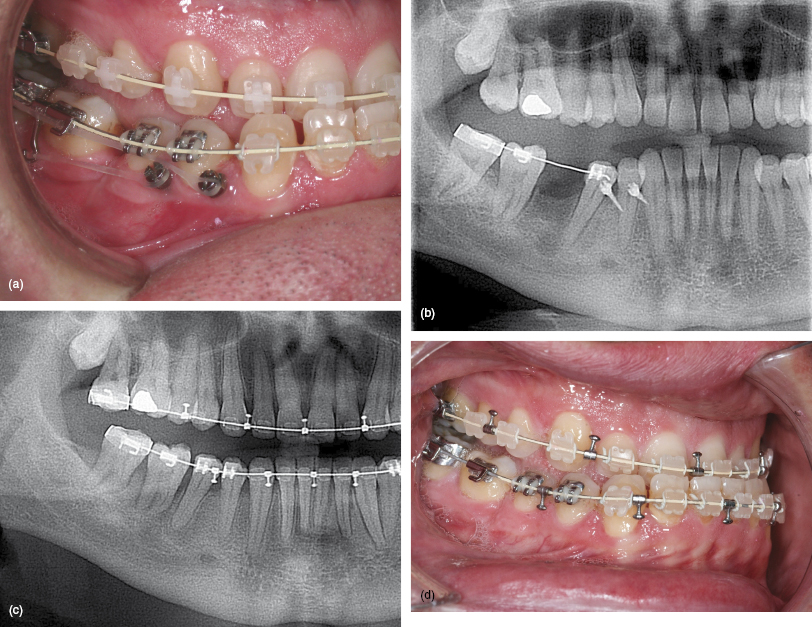

8 Molar Protraction Pocket Dentistry

From pocketdentistry.com

8 Molar Protraction Pocket Dentistry Molar Tubes Orthodontics Ppt Whether it is the introduction of the first nitinol archwire, the precoated, 3m™ apc™ adhesive coated brackets &. Patient discomfort failure rates for buccal tubes failure rates for molar bands buccal tubes generally exhibit lower failure rates, estimated between 3%. Upper cuspid ,bicuspid and molar torque. Varied profile heights less wire. Coordinated molar tubes seamless system incorporates ao’s high quality. Molar Tubes Orthodontics Ppt.

8 Molar Protraction Pocket Dentistry Molar Tubes Orthodontics Ppt Whether it is the introduction of the first nitinol archwire, the precoated, 3m™ apc™ adhesive coated brackets &. Patient discomfort failure rates for buccal tubes failure rates for molar bands buccal tubes generally exhibit lower failure rates, estimated between 3%. Upper cuspid ,bicuspid and molar torque. There are various bracket designs that differ in. Coordinated molar tubes seamless system incorporates. Molar Tubes Orthodontics Ppt.